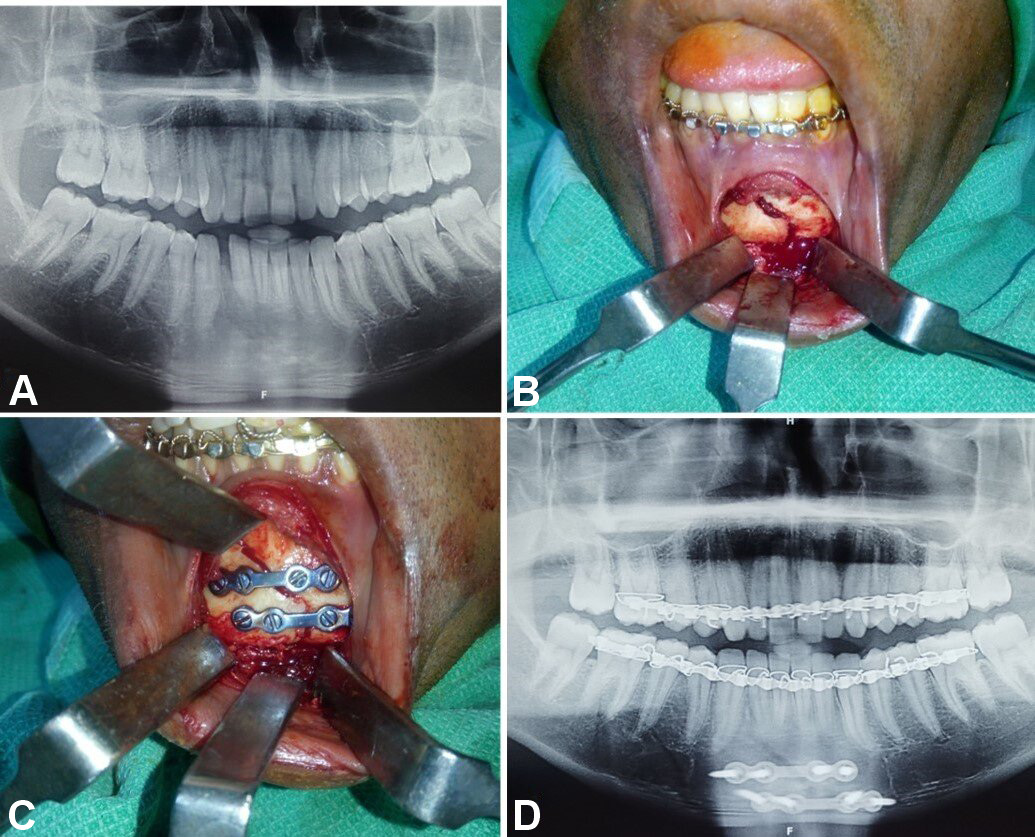

Patients with comminuted mandibular fractures, concomitant midface and dentoalveolar fractures, infected fractures, partial or complete edentulism, and systemic diseases were excluded from the study. Detailed preoperative medical and clinical examinations were conducted. The diagnosis of undisplaced or minimally displaced symphyseal or parasymphyseal fractures was based on clinical and radiographic assessments. Orthopantomograms were used to evaluate mandibular lower border displacement, with displacements of less than 5 mm included in the study (Figure 1). Advanced diagnostic techniques, including low-dose radiation and 3D assessments using computed tomography (CT), cone beam computed tomography and magnetic resonance imaging, facilitate comprehensive evaluation of head and neck disorders, including the assessment of both soft and hard tissue injuries.5, 6, 7 Therefore, CT with 3D reconstruction of the face was performed, with fractures exhibiting bucco-lingual overlap of less than 5 mm included in the study (Figure 1).

In group A, fixation was performed using 2 titanium microplates (0.8-mm, 4-hole design with a gap) and 8 microscrews (1.5 mm × 8 mm and 1.5 mm × 10 mm), which were placed subapically and at the inferior border of the mandible according to Champy’s lines of osteosynthesis (Figure 2, Figure 3, Figure 4).

In group B, fixation was conducted using 2 titanium miniplates (2.0-mm, 4-hole design with a gap) and 8 miniscrews (2 mm × 8 mm and 2 mm × 10 mm), which were positioned subapically and at the inferior border of the mandible according to Champy’s lines of osteosynthesis (Figure 5, Figure 6, Figure 7).